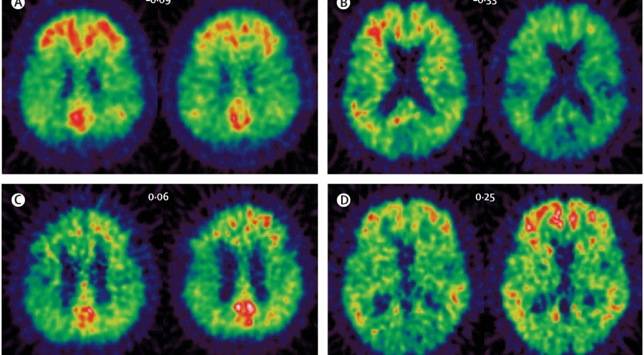

Una sola lesión cerebral -de moderada a grave- puede alterar las proteínas que regulan una enzima, asociada con la enfermedad de alzhéimer. El hallazgo, publicado en The Journal of Neuroscience , puede conducir al desarrollo de un tratamiento para retardar la progresión de la enfermedad. « ... La lesión cerebral traumática es uno de los principales factores ambientales de riesgo para la enfermedad de alzhéimer, ya que puede dar lugar a una disfunción en la regulación de la enzima BACE1 -el aumento en los niveles de esta enzima causa un nivel elevado de beta-amiloides, el componente clave de las placas cerebrales asociadas con la senilidad y la enfermedad de alzhéimer», explica la primera autora, Kendall Walker, del Departamento de Neurología de la Universidad de Tufts (EE.UU.).

Sobre la base de su anterior trabajo, la neurocientífica Giuseppina Tesco, de Tufts, dirigió un equipo de investigación que ha utilizado, por primera vez, un modelo in vivo para determinar cómo un solo episodio de LCT puede alterar el cerebro. En la fase aguda, primeros dos días, después de una lesión, los niveles de dos proteínas de tráfico intracelular (GGA1 y GGA3) se reducen, y aumenta del nivel de la enzima BACE1. Analizando muestras cerebrales post-mortem de pacientes con enfermedad de alzhéimer, los investigadores observaron que los niveles de GGA1 y GGA3 se redujeron, mientras que los de BACE1 eran elevados, en los cerebros de pacientes con alzhéimer, en comparación con los cerebros de las personas sin la enfermedad.

En otro experimento, utilizando una cepa de ratones modificados genéticamente para expresar un nivel reducido de GGA3, se observó que, una semana después de una lesión cerebral traumática, los niveles de la enzima BACE1 y los beta-amiloides se mantenían elevados, incluso cuando el nivel de GGA1 volvió a la normalidad. La investigación sugiere que los niveles reducidos de GGA3 son los únicos responsables del aumento de los niveles de BACE 1 y de, por tanto, la sostenida producción de beta-amiloides observada en la fase sub-aguda -siete días, después de la lesión.